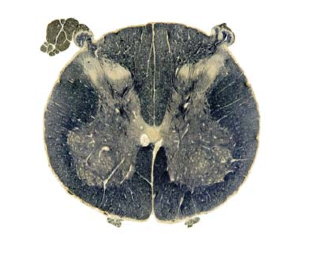

myelin stain of lumbar spinal cord; GM=WM approximately; note ventral enlargement